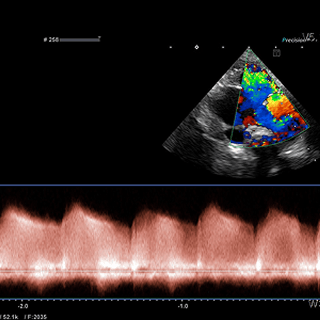

Cardiology & Nephrology

심장·신장 내과

정기 검진과 약물 치료로 노령 반려동물의 건강을 지킵니다.